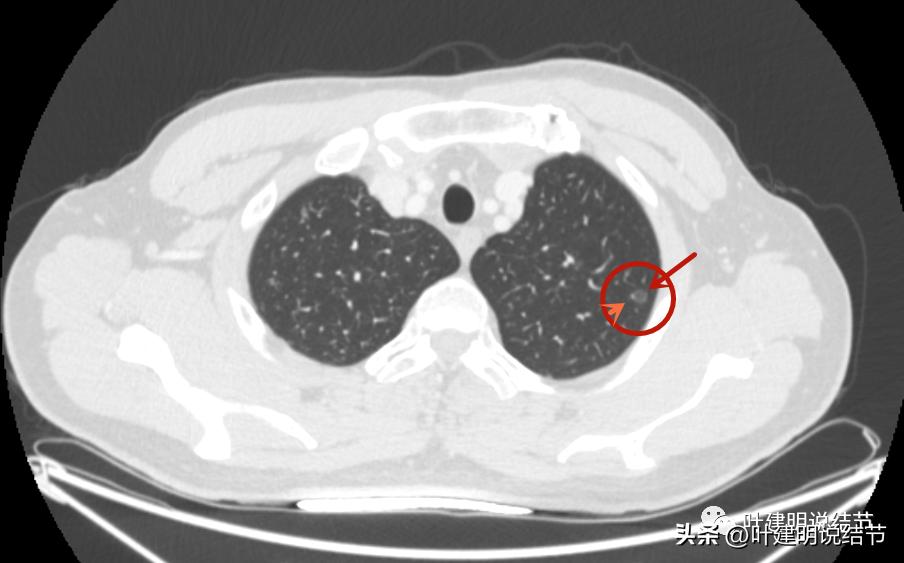

病灶1:左上叶结节

病灶出现,密度很淡,不仔细都看不太出来。

轮廓相对较清,是有结节在,密度低。

边上有小血管贴着,但病灶本身密度确实低。

病灶血管贴边,瘤肺边界较清。